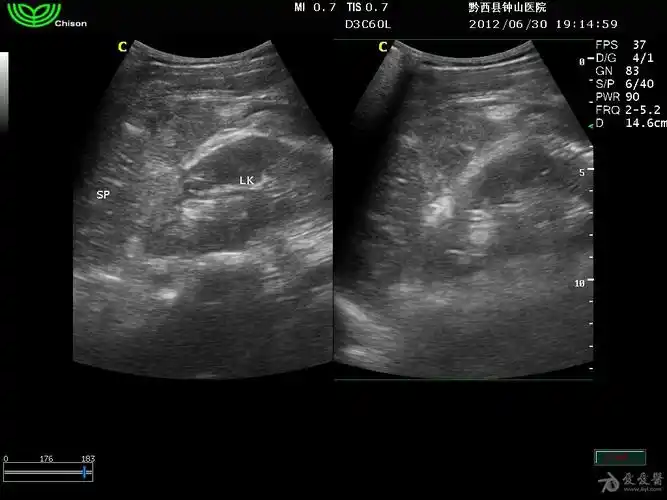

脾破裂图像收集 - 超声医学讨论版 - 爱爱医医学论坛 - 爱爱医医学网

脾包膜下破裂. - 超声医学讨论版 - 爱爱医医学论坛 - 爱爱医医学网

脾破裂——zengerya - 超声医学讨论版 - 爱爱医医学论坛

脾破裂4小时,无肿大. - 超声医学讨论版 - 爱爱医医学论坛

半夜来的脾破裂 - 超声医学讨论版 - 爱爱医医学论坛

脾破裂(脾内血肿),脾周血肿 - 超声医学讨论版 - 爱爱医医学论坛